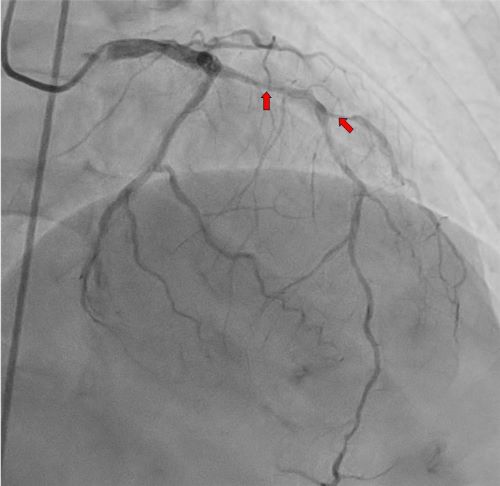

- ▲ 관상동맥.ⓒ세종충남대병원

특히 조기 퇴원이 가능했던 것은 인공심폐기 보조 없이 심장이 자발적으로 뛰는 상태에서 수술이 이뤄지는 무펌프 관상동맥우회술이 시행됐기 때문이다.급성심근경색증이나 협심증 등의 치료는 스텐트를 이용하는 심혈관중재술이 일반적 치료로 널리 알려져 있다.하지만 A씨처럼 동맥경화가 심해 스텐트 거치가 불가능한 경우 동맥경화에 저항성이 있는 체내 혈관을 채취해 막히거나 좁아진 부위를 우회해 주는 길을 만드는 관상동맥우회술이 도움을 줄 수 있다.관상동맥이 여러 군데 좁아져 있는 다중혈관 질환이나 심기능이 저하된 관상동맥 질환, 당뇨가 동반된 경우 등은 스텐트 시술보다 관상동맥우회술이 장기적으로 성과가 좋은 것으로 알려져 있다.수술을 집도한 흉부외과 한우식 교수는 “무펌프 관상동맥우회술은 고난도 수술이지만 환자의 조기 회복에 도움이 되기 때문에 세종충남대병원에서는 기본 전략으로 하고 있고 개인적으로도 80%를 무펌프로 시행하고 있다. 이는 서울 대형병원과 비교해도 차이가 없는 수치”라고 설명했다.그러면서 “환자들은 개심술에 대한 두려움이 앞서기 마련이지만 수술이 성공적으로 시행되면 대부분 1주일 전후의 입원을 거쳐 조기 회복해 퇴원할 수 있다”며 “세종충남대병원은 환자의 조기 회복에 중점을 두고 최선을 다할 것”이라고 강조했다.한편 세종충남대병원은 오는 12일 대동맥 판막 협착증에 대해 인조 판막으로 치환하는 두번째 개심술을 시행할 예정이다.